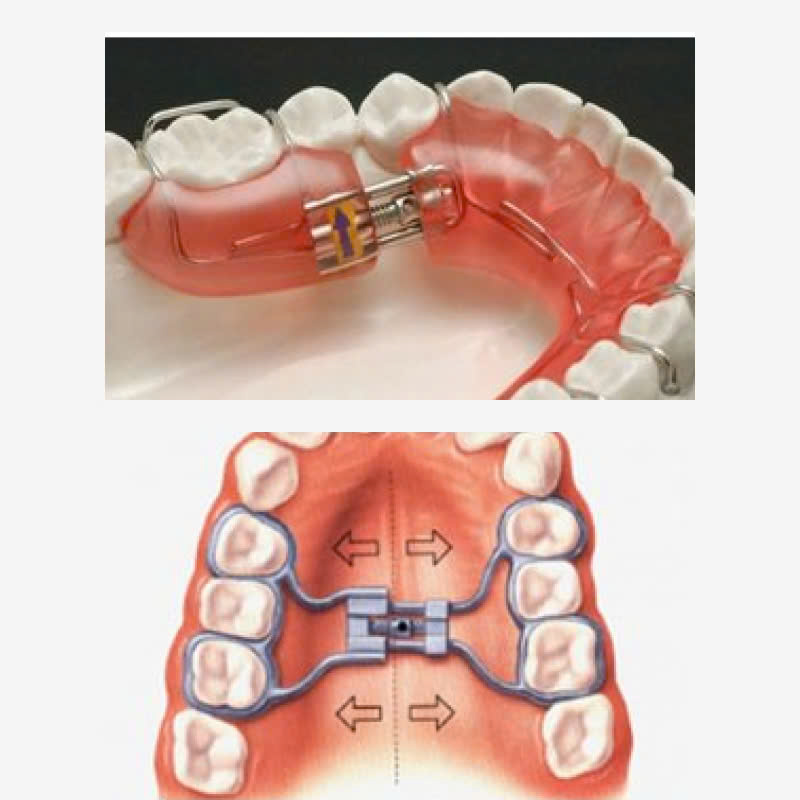

Bước 3: Thực hiện chỉnh hàm: Bác sĩ sẽ tiến hành chỉnh hàm dưới theo kế hoạch đã lập. Có thể sử dụng các phương pháp như: chỉnh nha, phẫu thuật hàm mặt…